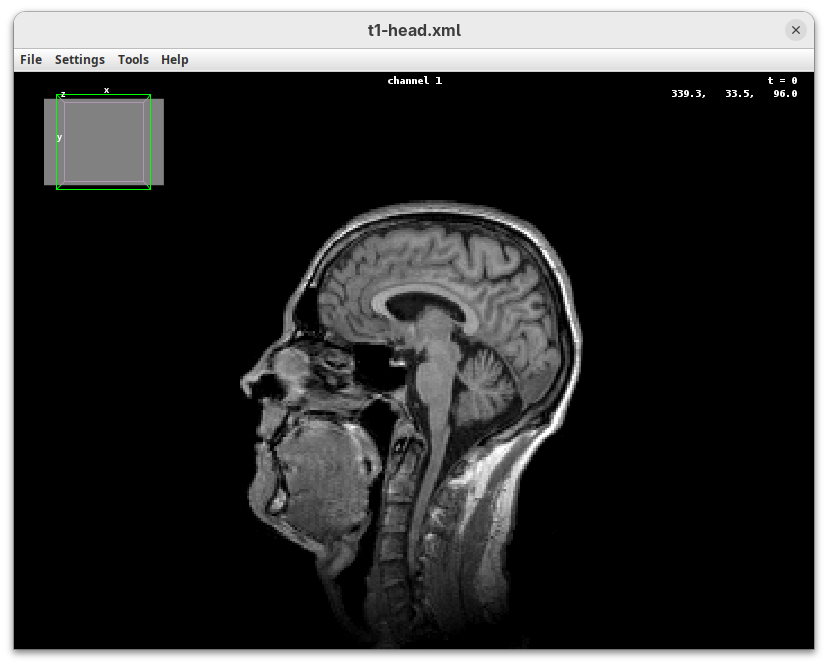

The BigDataViewer interface will open showing an optical section of the head sample.

Getting familiar with BigDataViewer is an essential skill for navigating large 3D datasets. It’ll also be important for the multiview registration pipeline. So, take the time to learn the basic commands and shortcuts. It is nicely intuitive. The BigDataViewer’s page on the ImageJ Docs has the official documentation and we can also go to Help > Show Help for an up-to-date overview.

Some of the movements to try:

Left-click and drag: turn the sample around the mouse pointer at any arbitrary angle.Right-click and drag: move the sample in the XY plane (of the view).Scroll: move through the Z plane (of the view). UseShift+Scrollto move fast.Ctrl+Shift+Scroll: zoom in or out.

But, most importantly, are the commands to put your sample back to its original orientation or along any of the original dimension axes:

Shift+Z: orient the sample on the XY plane.Shift+X: orient the sample on the ZY plane.Shift+Y: orient the sample on the ZX plane.

Finally, a visual tip. The default interpolation between image slices is nearest-neighbors. Press I to activate the tri-linear interpolation to obtain a much smoother (and improved) data visualization.